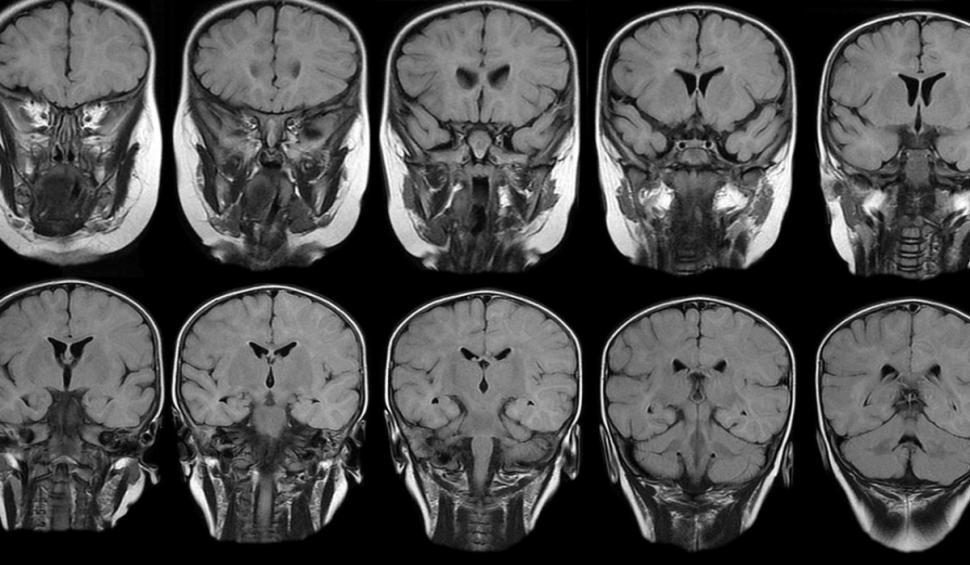

Echipa, condusă de oameni de știință de la Institutul Indian de Tehnologie din Delhi, a folosit un tip special de imagistică prin rezonanță magnetică (IRM) pentru a analiza modificările creierului cauzate de infecția cu SARS-CoV-2, virusul din spatele COVID-19, potrivit DCNews.

Imagistica ponderată cu sensibilitate (SWI) este o tehnică RMN relativ nouă. Funcționează profitând de răspunsurile diferite ale anumitor materiale din corp - cum ar fi componentele sanguine, calciul și fierul - atunci când sunt expuse la un câmp magnetic. SWI este deosebit de util pentru identificarea și localizarea hemoragiilor cerebrale, malformațiilor vasculare și tumorilor.

Echipa a analizat datele imagistice de la 46 de persoane care s-au vindecat de COVID-19 în ultimele șase luni, comparând acestea cu datele de la 30 de persoane sănătoase. Dintre pacienții cu COVID prelungit, simptomele pe care le-au raportat cel mai frecvent au fost oboseală, tulburări de somn, lipsă de atenție și probleme de memorie.

Rezultatele au arătat că supraviețuitorii COVID au prezentat anomalii semnificative într-un număr de regiuni ale substanței albe din lobul frontal, inclusiv girul frontal inferior orbital stâng și drept.